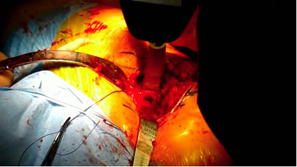

| Posterior approach. |

| Initial femoral neck resection high retained most of the neck. |